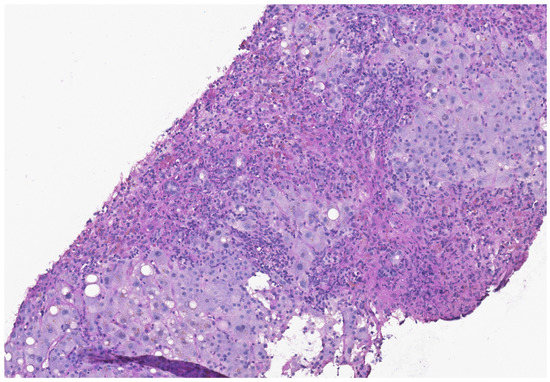

Nivolumab is a promising monoclonal antibody inhibitor of programmed death-1, a protein on the surface of T-cells. As such, it is approved for use in patients with multiple advanced malignancies and can significantly elongate progression-free survival. However, monoclonal antibody inhibitors can lead to [...] Read more.

Nivolumab is a promising monoclonal antibody inhibitor of programmed death-1, a protein on the surface of T-cells. As such, it is approved for use in patients with multiple advanced malignancies and can significantly elongate progression-free survival. However, monoclonal antibody inhibitors can lead to adverse hepatic reactions, which in rare cases result in further hepatic damage. Herein, we present a case of a patient with locally advanced gastric carcinoma treated with fluorouracil, oxaliplatin, docetaxel and the checkpoint inhibitor nivolumab. Five months after her first dosage of nivolumab and without a preexisting liver disease, she presented with transaminitis. During the course of her stay, the patient developed status epilepticus, which required mechanical ventilation followed by fulminant hepatic failure. A subsequent liver biopsy revealed severe liver damage with extensive confluent parenchymal necrosis corresponding to checkpoint-inhibitor-induced hepatitis. Alternative reasons for this hepatic failure were ruled out. Despite aggressive therapeutic interventions including corticosteroids and plasma exchange, the patient died due to liver failure. Although hepatic failure is rarely seen in patients with checkpoint inhibitor therapy, it requires early awareness and rapid intervention. Full article